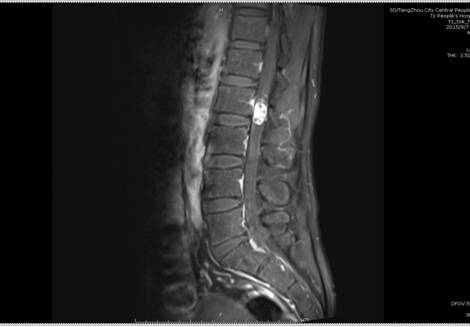

患者李某,男,40歲,因“右下肢疼痛、麻木8年余,伴腰部疼痛、活動受限1年余”入院,入院前患者曾在外院就診診斷為右側股骨頭壞死,一直予口服中藥治療,癥狀不見好轉,近1月來癥狀明顯加重。來我院行腰部MRI檢查示L2椎體水平椎管內占位,考慮良性神經源性腫瘤;L5/S1椎間盤突出;腰椎退行性變。神經外二科主任續繼軍帶領團隊仔細評估患者術前狀態,多次進行病例討論,認為患者手術指征明確,但手術風險較大,容易引起下肢癱瘓、大小便失禁等并發癥。患者正值青壯年,為家庭中支柱,一旦喪失勞動力,對整個家庭將是災難性打擊。

術前影像學檢查